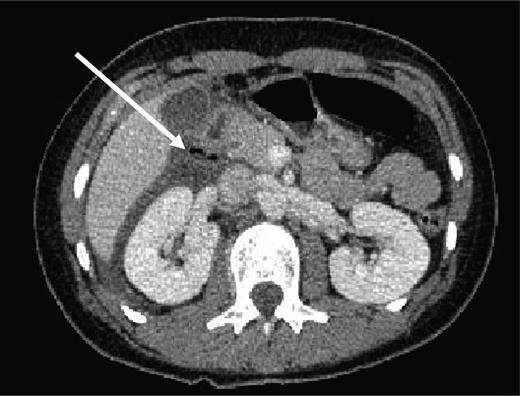

A 19-year-old girl presented to the Emergency Department at 1 am after having a football kicked from a distance of 5–10 m into her abdomen 7 h previously whilst watching a game. She complained of worsening diffuse abdominal pain and vomiting. Her observations were stable; however, on examination, her abdomen was diffusely tender and there was evidence of generalized peritonism. She had a white cell count of 18.8 × 109/l, but the rest of her blood tests, including amylase, was normal. Her chest radiograph did not show any evidence of free air under the diaphragm. A computed tomographic (CT) scan of her abdomen and pelvis was arranged, which showed abnormal areas of low attenuation and multiple pockets of air in the right flank, surrounding the right kidney and in the right sub-hepatic space, consistent with a perforation of either the ascending colon or the duodenum (Fig. 1). A laparotomy was performed and a 0.5 cm perforation was seen in the antero-lateral border of the duodenum at the junction of the first and second parts of the duodenum following kocherization. The perforation was oversewn and repaired with an omental patch. She recovered well from the operation and was discharged 4 days later.

CT of abdomen showing free air in right para-renal space (white arrow).